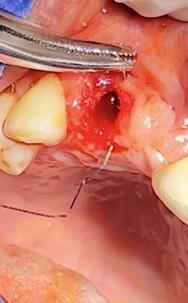

Figura 8. Irrigación del alveolo con solución fisiológica y sutura simple en la mitad del alveolo.

Elaboración: Los autores.

Finalmente se prescribió al paciente ibuprofeno de 600 mg por cuatro días, se le manifestó instrucciones postoperatorias y control para remoción de puntos en una semana.